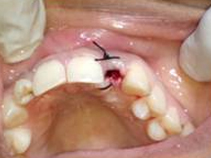

Use of Bone Graft & GTR membrane for an Implant

Suturing after Bone Grafting